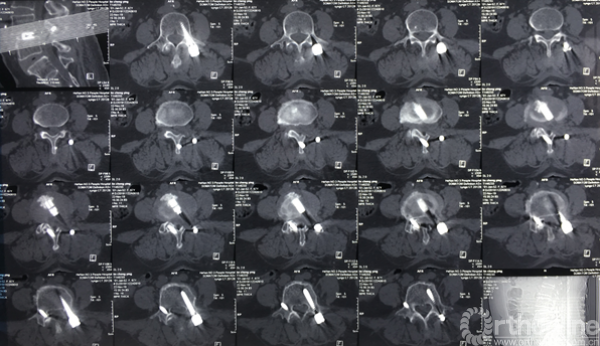

术前CT示:1.腰椎退行性变;2.L4椎体滑脱;3.腰椎管狭窄症;4.相应神经根硬膜囊受压。

术前CT